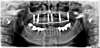

Radiographie panoramique de la première intervention avec greffe osseuse et pose de 4 implants. Les implants sont stables et la gencive est refermée. Photo a 48 h

4 mois après,l'os recouvre la totalité des implants, le reste des dents est extrait et les deux derniers implants sont posés. Une empreinte est réalisée et la prothèse fixe est vissée sur les implants le soir même.